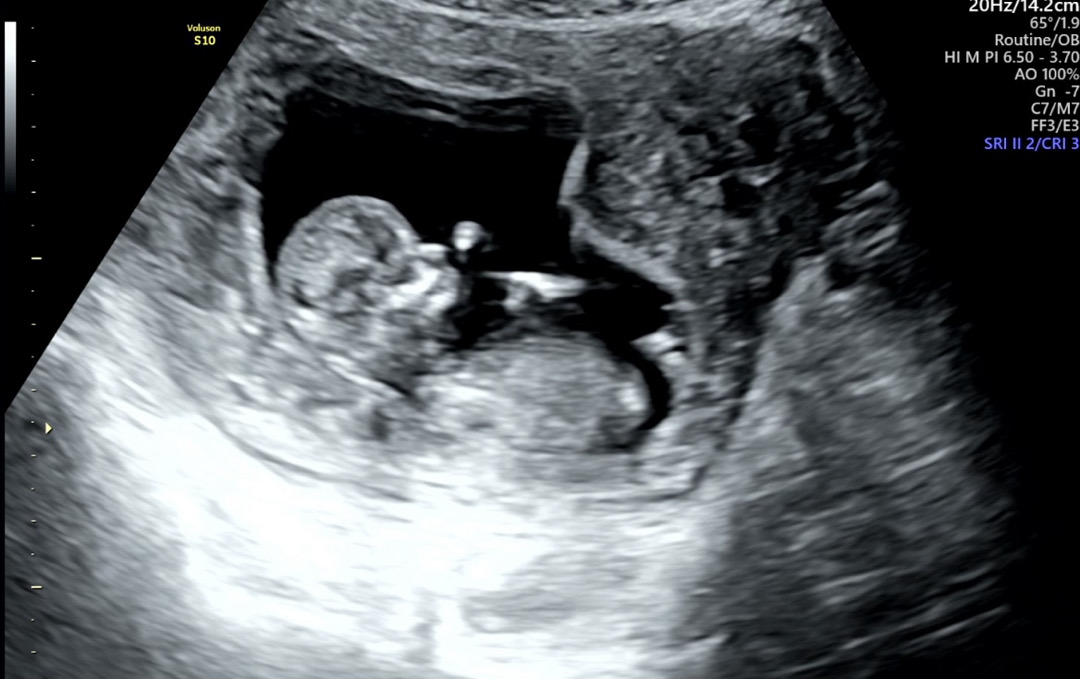

각도법 봐주실 수 있는 사진인가요~?

각도법 볼 수 있는 사진인가요~? 궁금하네요 ㅎㅎ

딸일 가능성이 좀더 커보이는데요?

저도 여러모로 딸일거같은 느낌이 들기는합니다..ㅎㅎ 감사합니다☺️